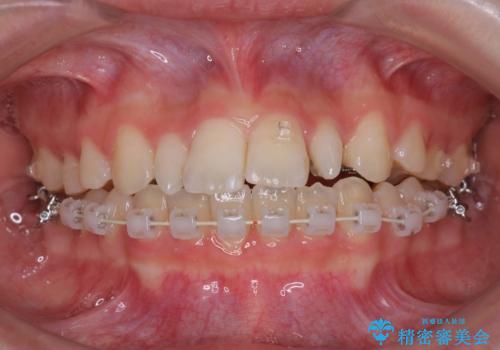

- 矯正装置

- ハーフリンガル

- ハーフリンガルシステムによる矯正治療を行いながら、スペースコントロールをみて前歯を仮歯へ

→矯正の終了をメドに仮歯をセラミックへ置き換える